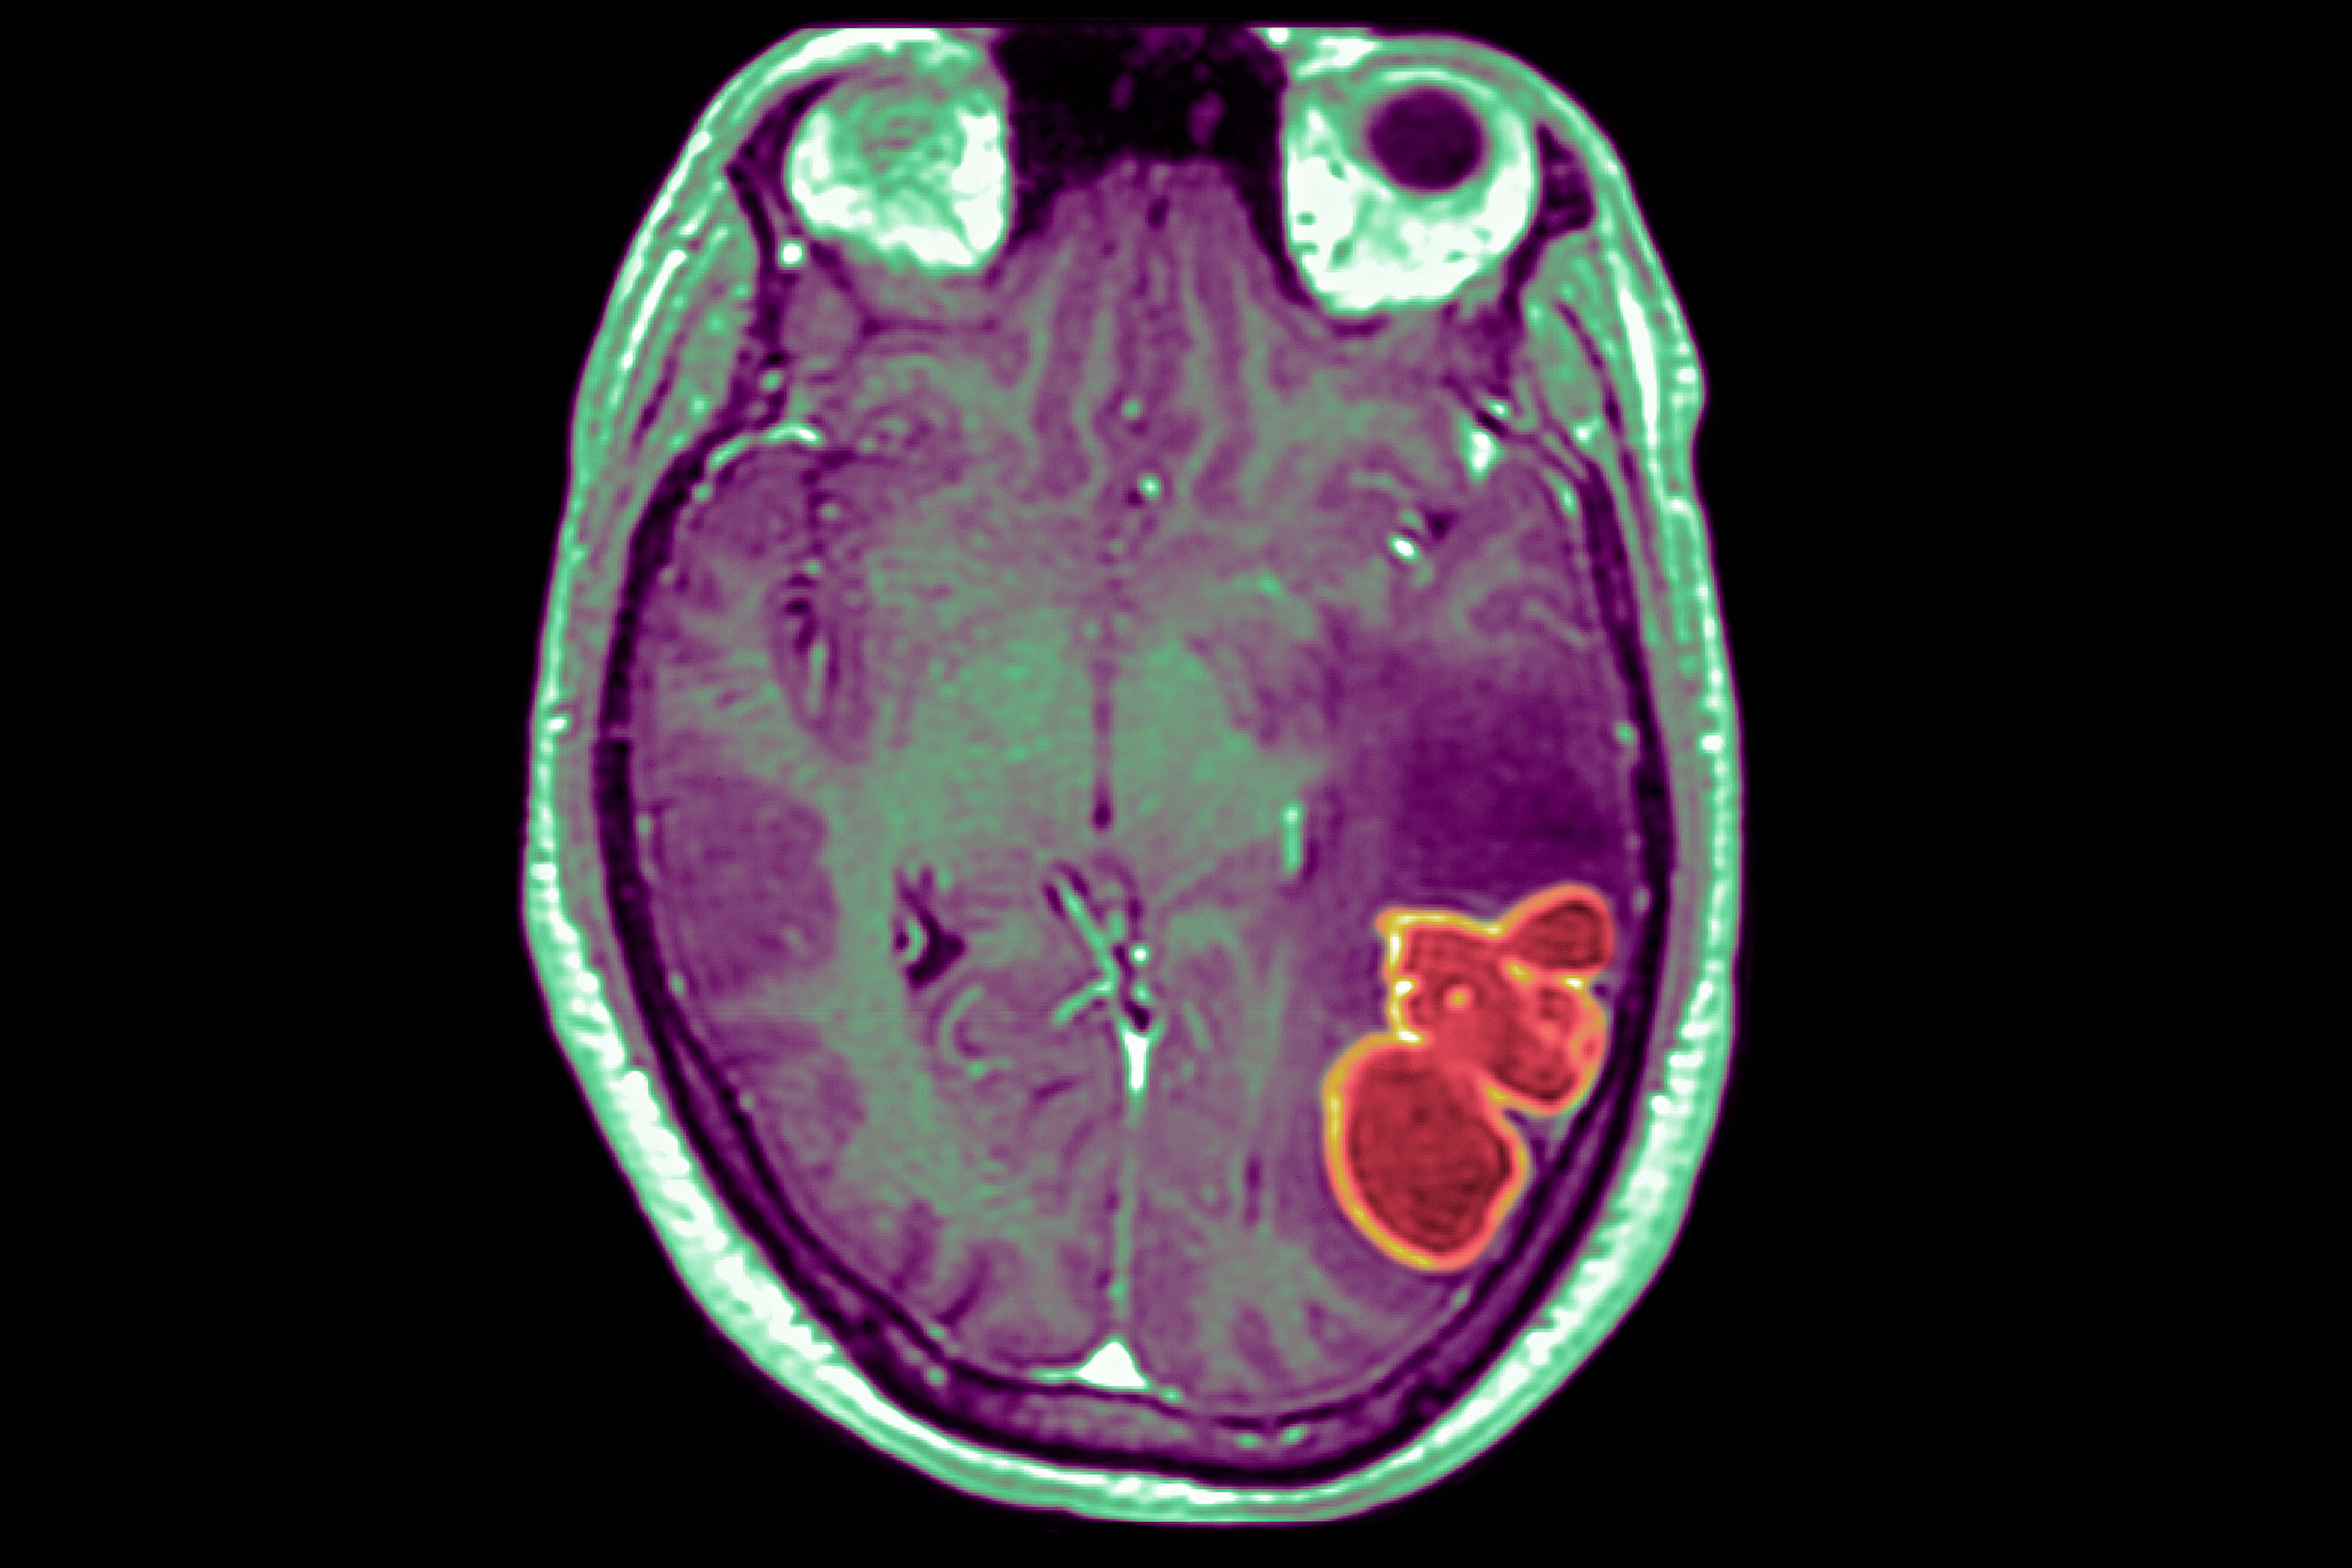

Brain abscesses are pus-filled pockets of infection that spread to the brain. They can cause seizures, visual disturbances, or changes in vision, speech, coordination or balance. The earliest symptoms are headaches and a fever that comes and goes. Abscesses often require several surgeries to treat, and kids may spend weeks or even months in the hospital recovering after they have one.

About a third of the brain abscesses in the Clark County cluster were caused by a type of bacteria called streptococcus intermedius that normally hangs out harmlessly in the nose and mouth, where our immune system keeps it in check. But when it gets into places it shouldn't be, like the blood or brain, it can cause problems.